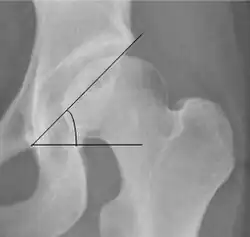

| Tönnis angle |

|

Slope of the sourcil (the sclerotic weight-bearing portion of the acetabulum) | 0 to 10°

| Caput-sourcil angle[12] |

Superior to the Tönnis angle in cases without joint space narrowing or subluxation.[12] The medial point of the sourcil is defined as being at the same height as the most superior point of caput femoris. | −6 to 12°[12]